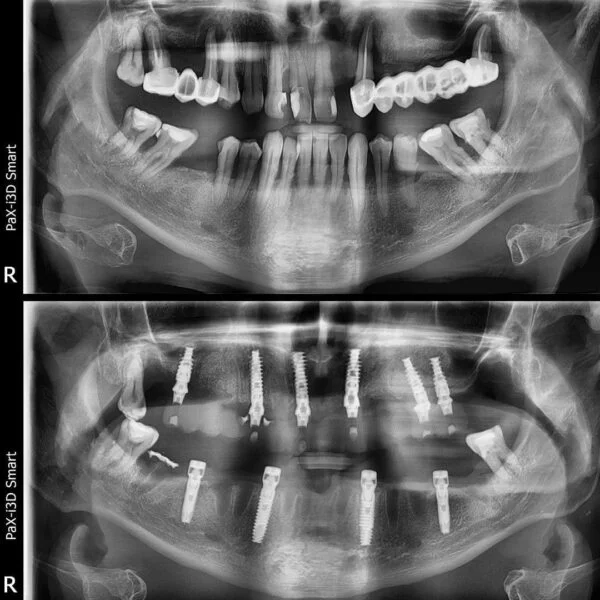

Implantul dentar este adesea recomandat deoarece prezintă foarte multe avantaje, iar, de multe ori, este unica soluție pentru protezarea unei edentații.